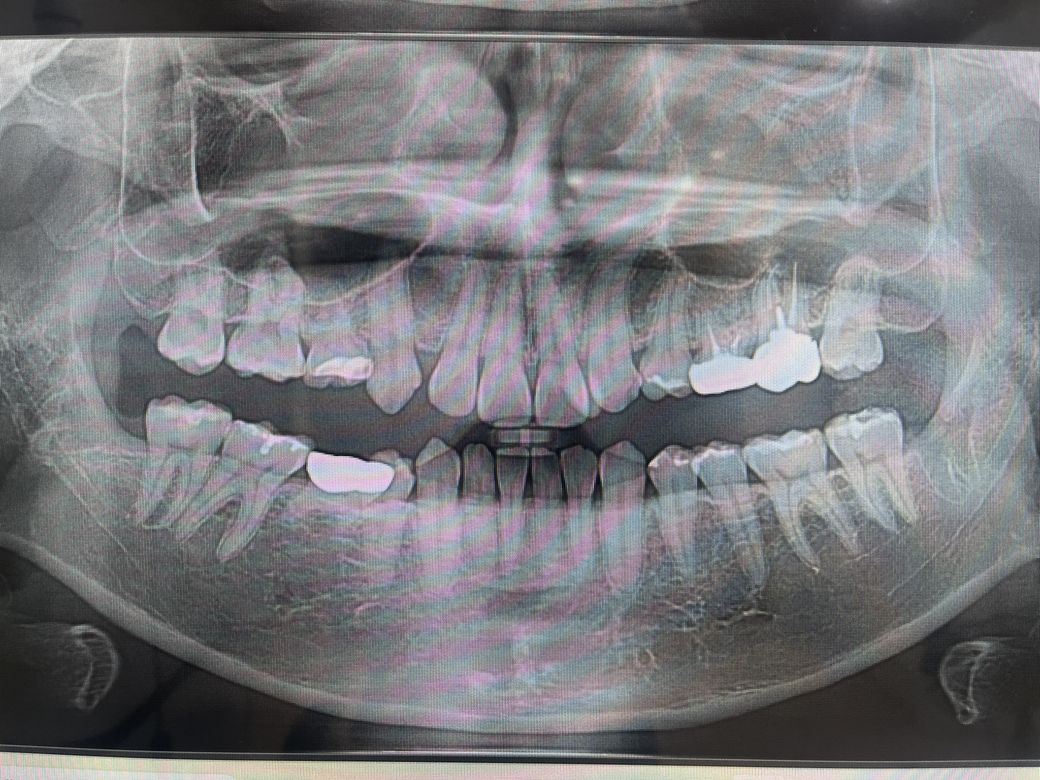

이빨 전체적인 상태가 어떤지 궁금합니다

최근에 밑에 사랑니들도 다 발치했고 아말감 제거후 인레이, 여러치아들 레진치료까지 해서 할 수 있는

것들은 거의 다 완료한듯 싶은데

제가 이빨 개수 자체도 부족하고 나올 영구치가 부족해서 아직도 유치로 쓰고 있기도한데

그냥 엑스레이 사진상으로 봤을때는

어떠한 상황인지 궁금해서 한번 올려봅니다

참고로 윗니에 과잉치가 있는데 이 과잉치가

원래 제자리에 나왔어야 할 송곳니인지도 궁금해요

교정치료 자체는 괜찮아보입니다. 없는 치아도 있고 장기적으로 관리 잘 해줘야 할 듯 합니다.

엑스레이 상으로는 크게 문제가 없어 보입니다. 영구치가 2개정도 없어서 유치를 사용하고 계시는거 같으니 최대한 조심히 사용하시는게 좋을것같습니다.

1. 사진상 왼쪽 아래 젤 뒤 어금니 한번 충치 체크해보시고 그외 나머지는 괜찮아보입니다

2. 영구치결손으로 남는 잔존유치 3개는 어쩔수 없습니다 쓸때까지 쓰는 방향으로 하는게 좋을 것 같습니다

3. 사진상 과잉치는 송곳니와는 관련 없을 것 같습니다